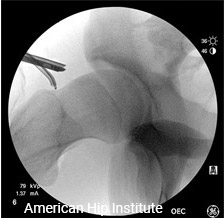

Surgery Observation

Contact us at info@americanhipinstitute.com to schedule observations.